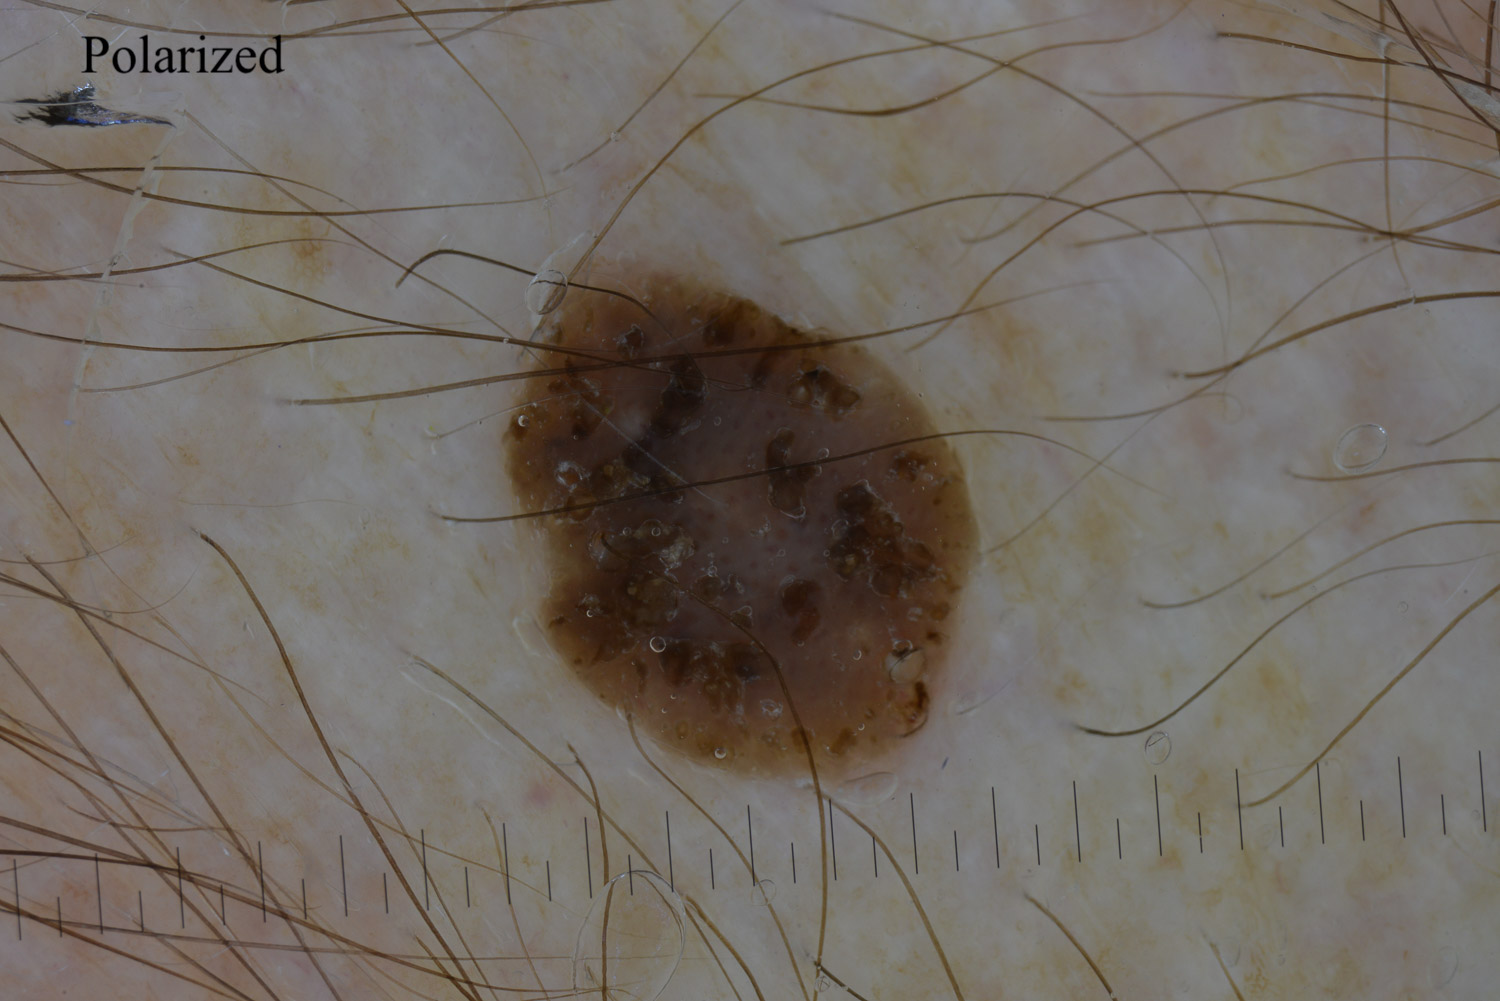

Case: 253

To view the image full-screen and open it in a new tab, please click on the image (thumbnail).